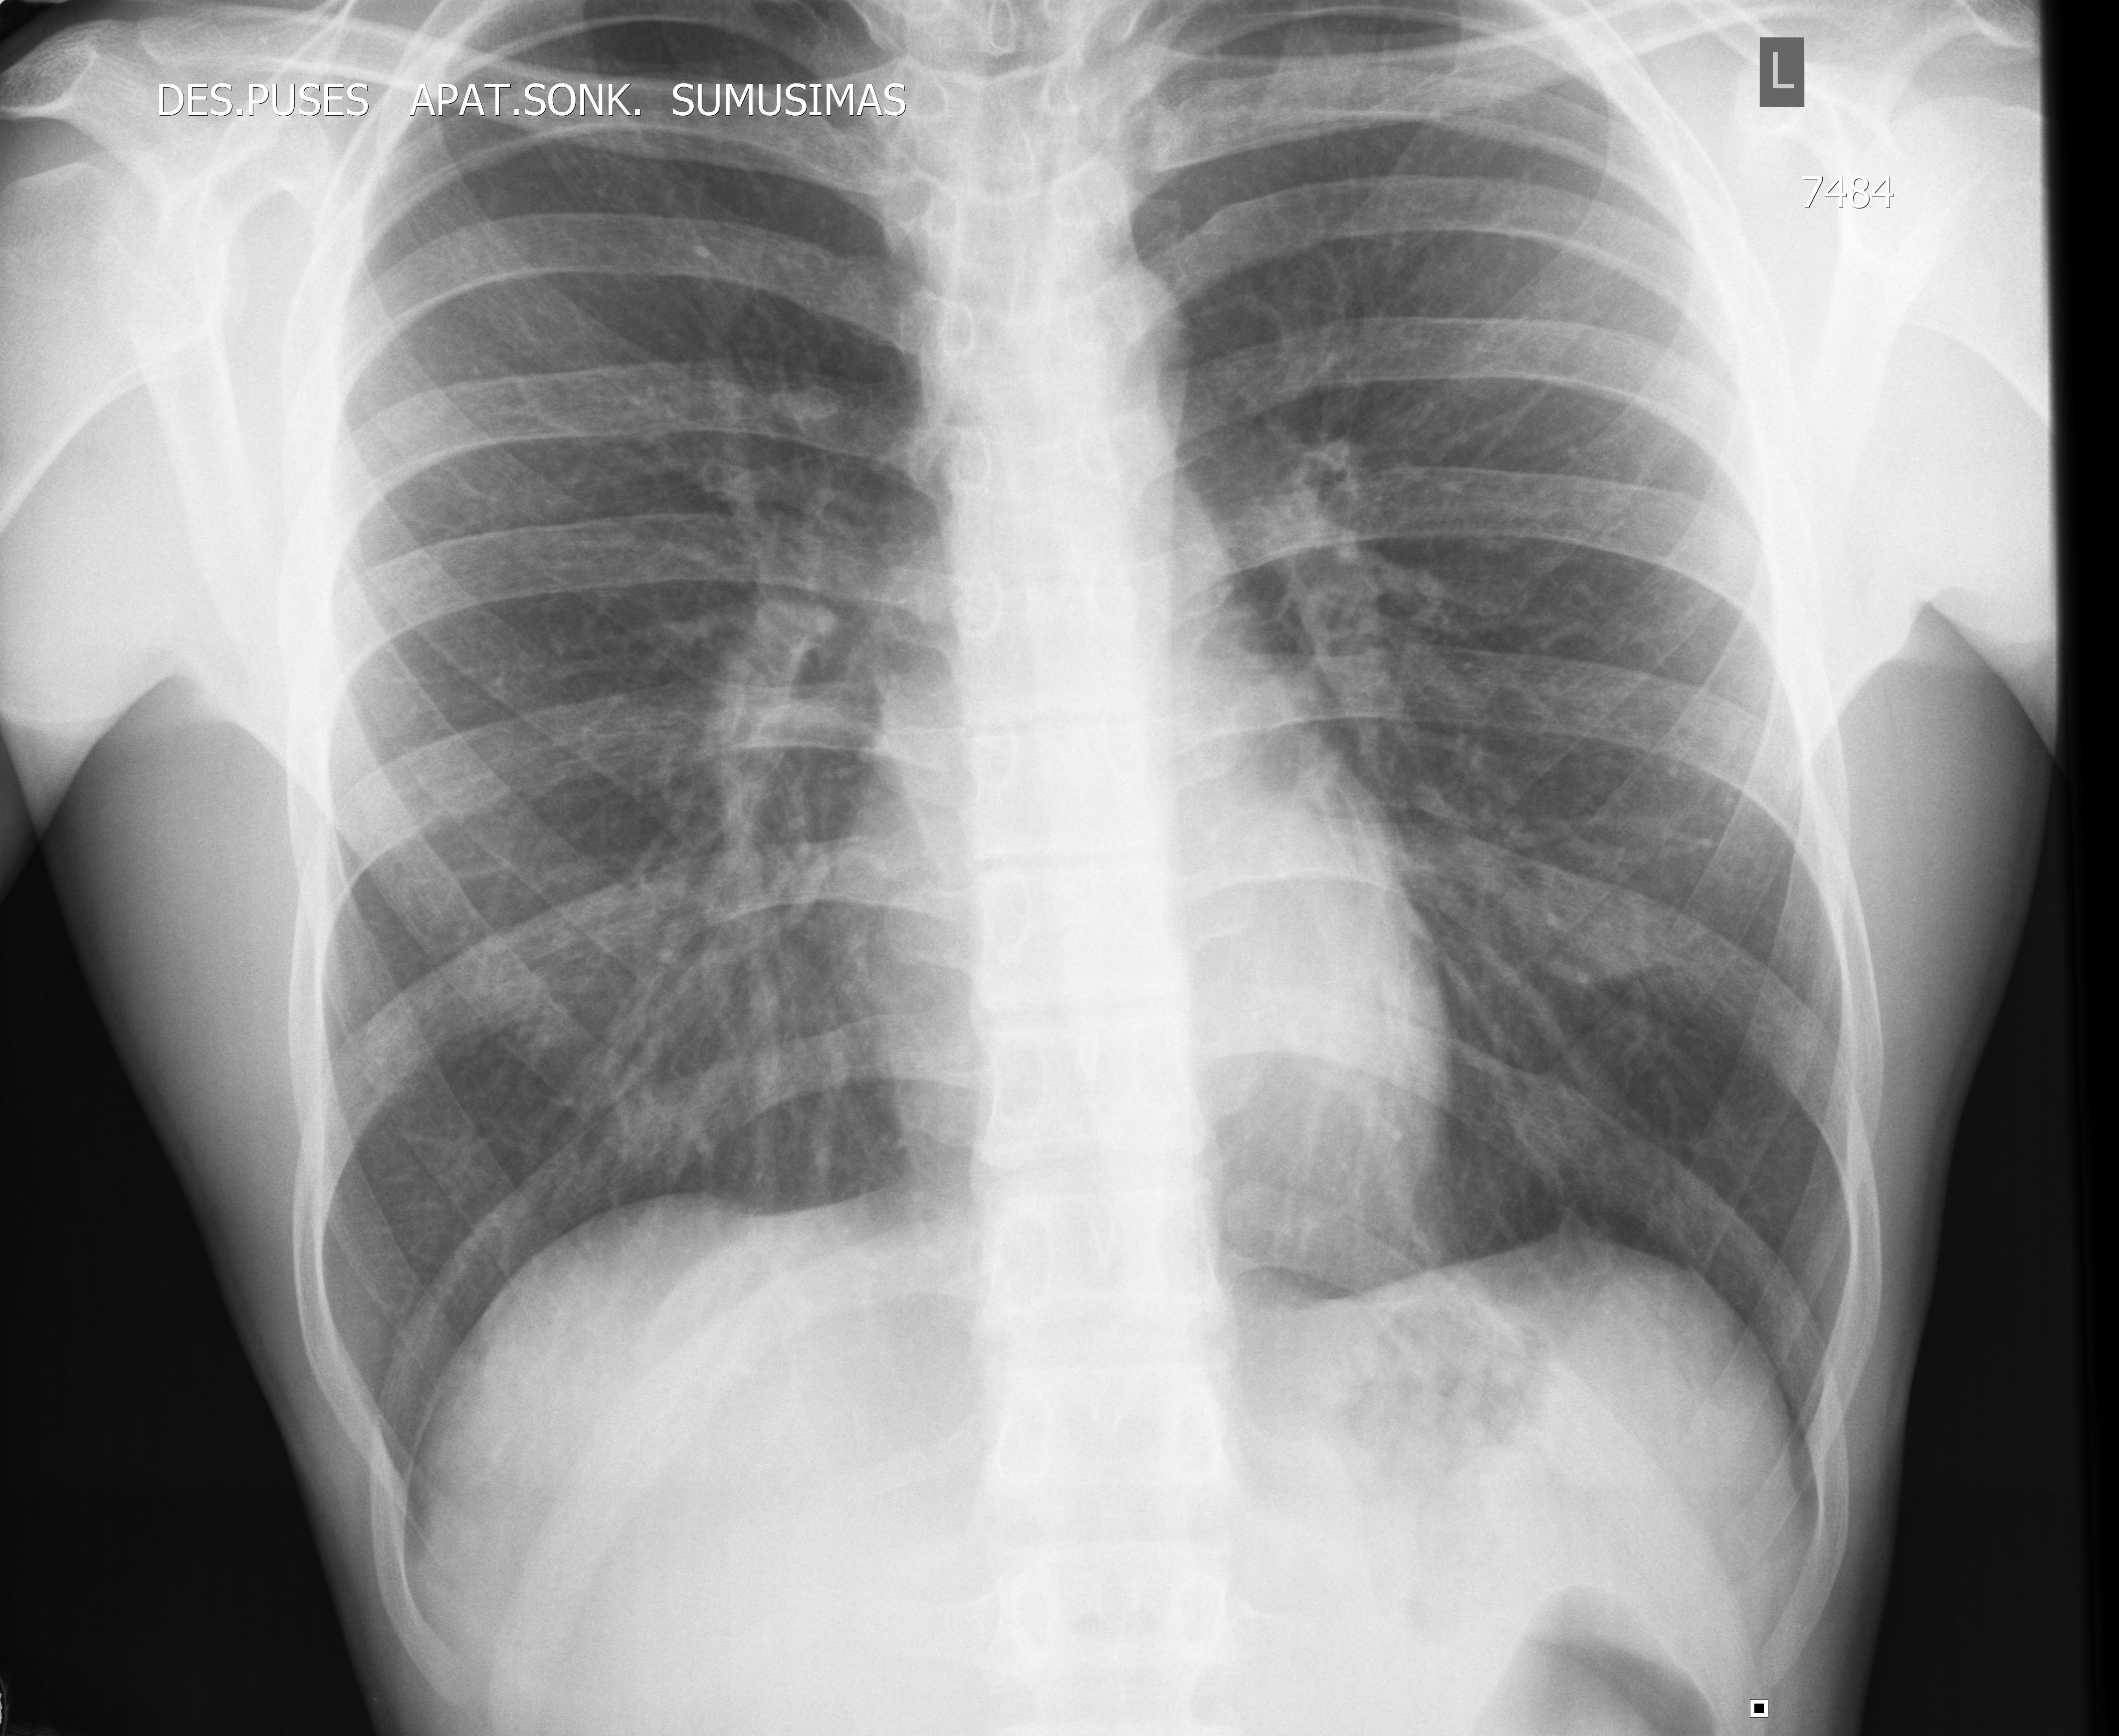

#5 Перелом ребер, УЗИ. Rib fracture, sonography. Šonkaulio lūžis.

19y M